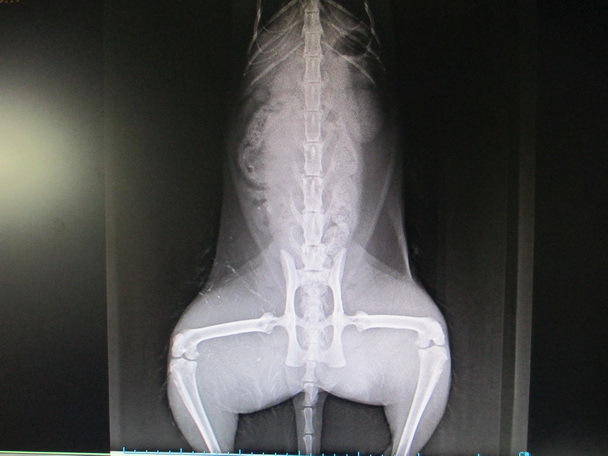

主題: 車禍失溫的黑白貓 申請者姓名: 楊溫蒂 花色: 申請日期: 2012-12-22 18:46:23 申請者部落格: 申請者臉書網址: 所在縣市/合作醫院: 台北市/欣旺動物醫院 治療費用: 10200元 需求人數: 11人 已結案 (2013-08-06 13:45:59) 報名人員: Jill(已付款)、Uu、Jane Chen(已付款)、Clain Lin(已付款)、WeiLin Chen(已付款)、韋恩咖啡、黃立皮(已付款)、sasa(已付款)、Ekim Lu(已付款)、Jess(已付款)、OLivia Lee(已付款)、黃先生、Fubii Su Fubii Su、Mia Wei(已付款)、Mao Guai(已付款)、 候補人員: Alex.Tsai、 動物病情說明: 滷蛋是這隻黑白公貓的名字.牠是前一陣子TNR的貓.平日魯蛋都是在住家對街小吃店附近活動.很少會離開過馬路.12/1早上7點多下樓要去買菜時聽到滷蛋哀號的叫聲.循著叫聲找到滷蛋.發現牠躲在車下.下半身不會動.疑似被車撞.於是趕緊回家拿網子撈.緊急就醫.送醫發現滷蛋下半身癱瘓.體溫35.7.隨時有可能會休克.醫生緊急幫滷蛋保溫上點滴.並照X光.還好滷蛋沒有骨折.但需要一段時間修復......經過3星期治療滷蛋恢復體溫.食慾.但下半身還需要一段時間恢復.目前滷蛋帶回照顧中.